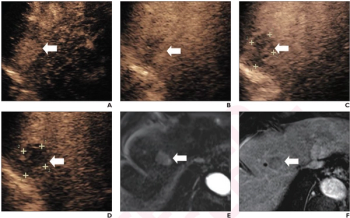

Emerging research showed the combination of contrast-enhanced ultrasound (CEUS) with perfluorobutane and modified 2017 LI-RADS criteria had comparable sensitivity, specificity, and accuracy to current magnetic resonance imaging (MRI) and computed tomography (CT) approaches to detecting hepatocellular carcinoma (HCC) lesions.